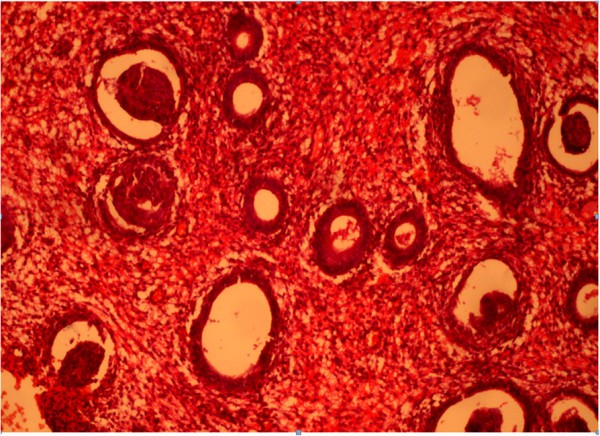

Pathological proliferation of the endometrium, which loses hormonal hyperplasia characteristics and has the emergence of patterns inherent to malignant tumor, is called atypical endometrial hyperplasia. According to the degree of prevalence, diffuse and focal types are distinguished; according to the proliferation of glandular and stromal components, simple and complex forms are distinguished.

Histologically, we determined in atypical endometrial hyperplasia the glands with numerous ramifications and papillary projections that protruded into the lumen of glands; they are strongly sinuous, with irregular shape. Here and there, glands are closely located to each other without stromal layers and are separated by a narrow strip of connective tissue only. The epithelial cells of glands acquired the features of tumor processes: reduction of nuclear/cytoplasmic ratio, hyperchromatosis, nuclear polymorphism, etc. There were proliferation and increased mitotic activity and abnormal mitosis. Atypical endometrial hyperplasia is shown in Figure 12.

Figure 12

Atypical glandular hyperplasia of the endometrium. Coloring by hematoxylin-eosin (×40).

The content of estradiol receptors in patients with atypical hyperplasia was significantly different from that of the control group, as estradiol receptors in the epithelial cells with atypical hyperplasia amounted to 65.2%; in the stroma, 42.6% (in the control, they were 43.3% and 29.6%, respectively; Figure 13).

There was a significant difference in the content of progesterone receptors in the endometrial stroma (81.8%), which was characterized by a sharp increase in what we believe was a prognostic criterion for determining the subsequent treatment strategy. Percentage of progesterone receptors in epithelial cells was 44.3%, whereas in the control, it was 52.4%. The increased concentration of progesterone receptors in the stroma was probably due to relative hypoprogesteronemia and thus was compensatory anti-proliferative in nature.